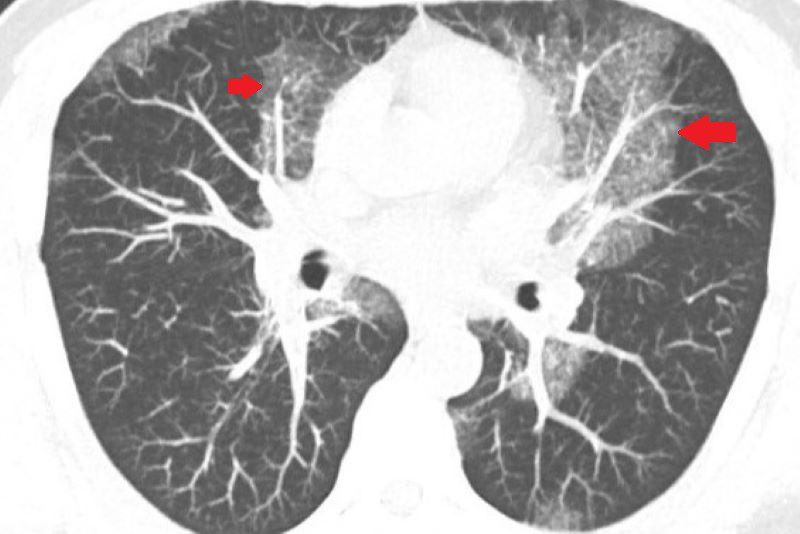

40歲的魏先生一向體格健壯,從事搬運工作多年,體能不輸年輕人。然而,近兩年來他逐漸感覺力不從心,肺活量明顯下降,時常出現間歇性暈眩,甚至有數次在搬運重物時,突然吸不到氣,胸口像是被重物壓住般喘不過氣來。近期他更在平時活動中出現背部劇烈疼痛,這才引起他的警覺,前往診所檢查,意外發現肺部有大片白影,隨即轉診至台北慈濟醫院胸腔內科。藍冑進主任與醫療團隊全面評估,電腦斷層初步研判為肺部慢性發炎,但進一步的支氣管鏡檢查卻顯示氣道清晰無異常,連同細菌與黴菌等各項培養檢查也均為陰性,病因成謎,只能密切追蹤病況,但三個月後卻發現雙肺白影惡化,最後,魏先生接受電腦斷層導引下的肺部穿刺切片,確診為極為罕見的肺部蛋白質沉積症(Pulmonary Alveolar Proteinosis, PAP)。

魏先生的胸部影像檢查有大片白影。